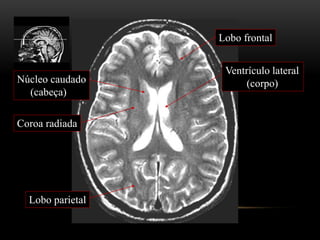

Lobo frontal

Ventrículo lateral

(corpo)

Coroa radiada

Núcleo caudado

(cabeça)

Lobo parietal